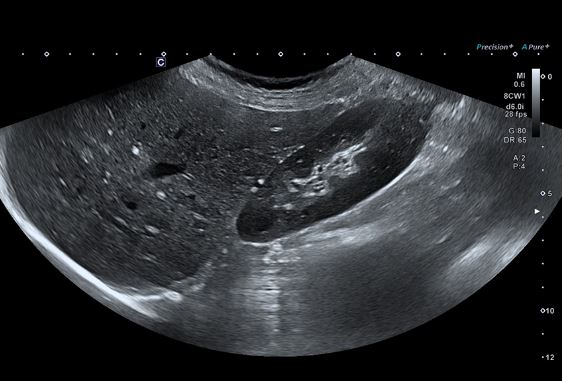

Ультра широкий огляд печінки та нирок надає більше інформації в одній площині.

Конвексний датчик PVU-574BT (10C1)

Високочастотний монокристалічний конвексний датчик забезпечує високу просторову роздільну здатність і проникнення для підвищення клінічної впевненості в акушерських, неонатальних та інших дослідженнях.